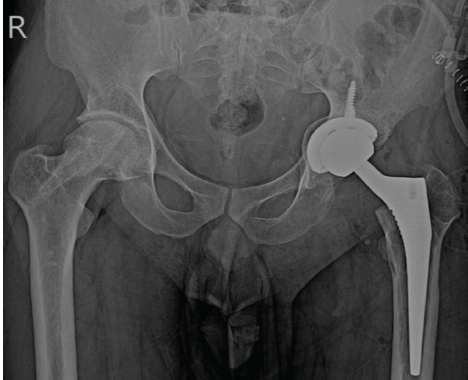

His CRP was 9.1 g/L, and his WBC count was normal (Table 1). His creatinine was 1.26 mg/dL, albumin was 4.3 g/dL, and there was no proteinuria. Ultrasound of the hip did not show any fluid. After withholding tacrolimus for a week, he underwent uncemented total hip replacement (Fig. 3) under the cover of piperacillin and tazobactum 4.5 g thrice daily.

Figure 3: Left uncemented total hip replacement status.